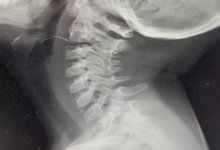

С проволокой в горле жила малышка целую неделю

Медикам удалось ее спасти.